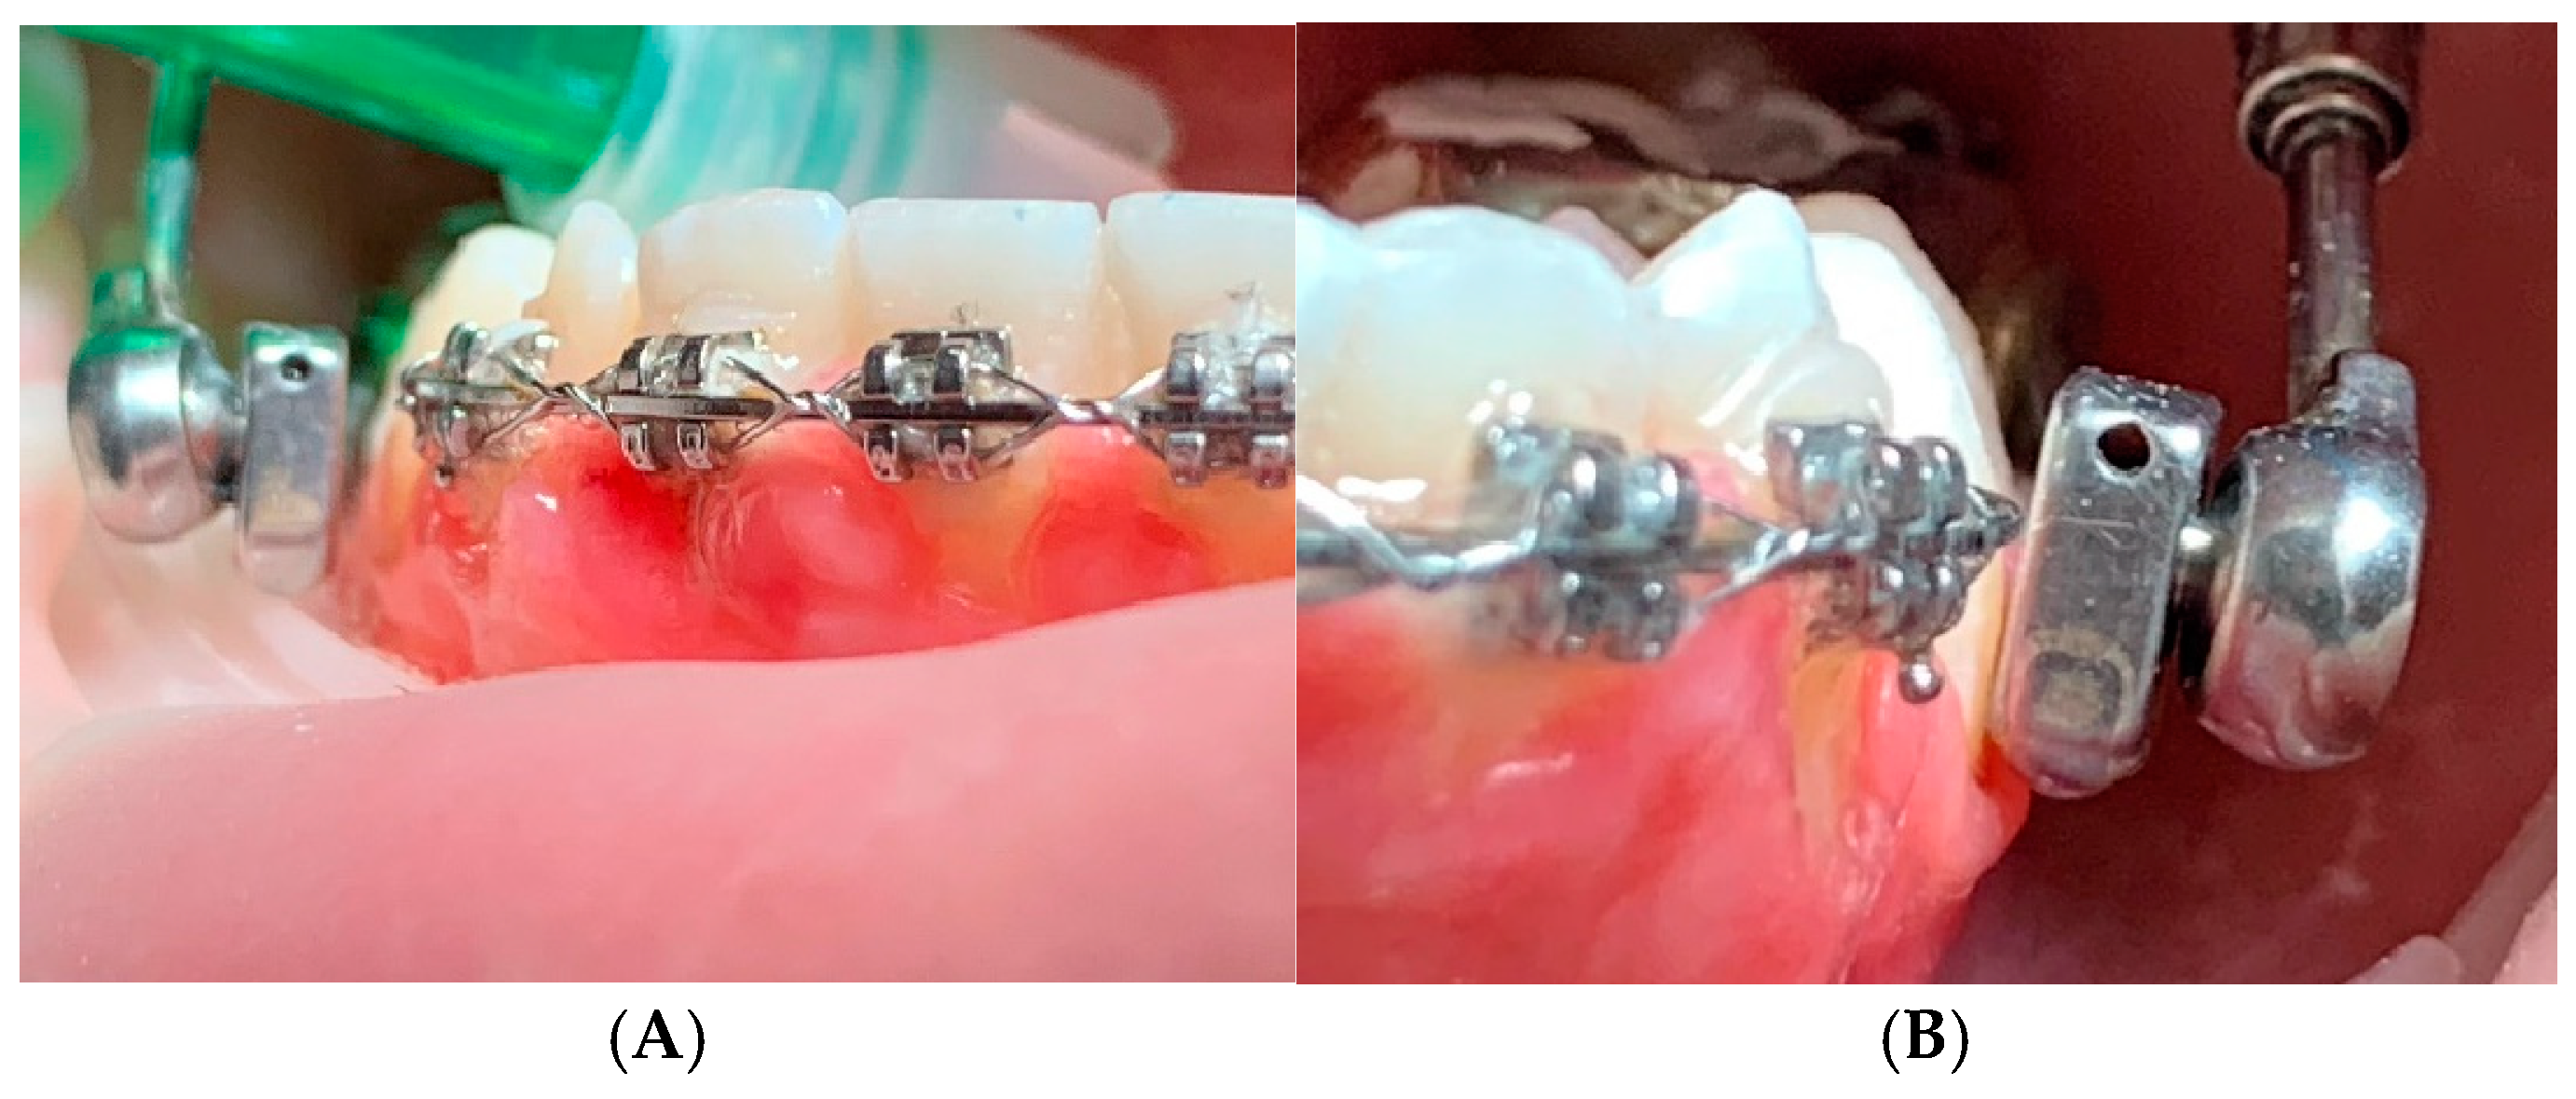

The increased overjet (compared to what is usually brought to 0 mm) allows for faster achievement of intercuspation. After a week the overjet will have increased and will allow the intercuspation of the posterior teeth. In this period of time the dentoskeletal system and the neuromuscular system undergo adaptive phenomena that allow the dental arches to return to contact. Even with this modification to the classic protocol, there is the possibility of reactivating the device weeks later, when normally there is a mild recurrence (1-2 mm) of class II. So since it does not affect this aspect, our goal is to obtain molar intercuspation as quickly as possible which would be much slower with overjet brought to 0 mm. Therefore, after approximately 1 week the patient presents an occlusion of numerous teeth in contact with maximum intercuspation. This phase of muscular and joint adaptation is clinically visible in the photos of the patients as soon as the device is cemented in the mouth and subsequently at the check-up after 7 days: initially the muscles appear "forced" to maintain the protruded position (an aspect common to many functional devices including the Frankel), while the muscular posture improves significantly already after a week when intercuspation has been obtained (

Figure 4 A,B,C).

The spatial instability of the metal elements can also occur on the lower arm welded to the band of the lower molar: in fact the application of the muscular force which has the anterior joint as its fulcrum determines the creation of a lever arm which discharges its force on the lower molars: slight displacements of the terminal part of the arm can be observed which can create a direct mucosal decubitus or due to secondary vestibularization of the first premolar which cannot be controlled by wire sectionals on the MBA (

Figure 6 A,B).